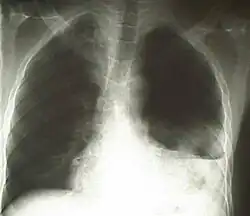

Linksseitiger Hämatothorax

Unter Hämatothorax, auch Hämothorax genannt, versteht man eine Ansammlung von Blut im Pleuraraum. Es handelt sich um eine exsudative[1] Form des Pleuraergusses.

Diagnostisch zeigt sich eine Kombination von Dyspnoe sowie pathologischem Auskultations- (abgeschwächtes bzw. fehlendes Atemgeräusch) und Perkussionsbefund (hypersonorer Klopfschall). So kann mit hoher Wahrscheinlichkeit ein Hämato- bzw. Pneumothorax vermutet werden.[6] Ein Röntgen oder CT des Thorax dient der Bestätigung der Verdachtsdiagnose.[7] Im Röntgenbild kann jedoch nicht zwischen Hämatothorax, Pleuraerguss, Chylothorax und Pyothorax/Pleuraempyem unterschieden werden, deswegen erfolgt die sichere Diagnose meist mittels CT. Im Schnittbild kann eine eindeutige Identifizierung mittels der Dichtewerte (HE) erfolgen.[8] Wenn sich bei einer Pleuraprobepunktion ein blutiges Punktat zeigt, sollte der Hämatokrit des Punktats bestimmt werden. Übersteigt dieser 50 % des Hämatokritwertes des peripheren Blutes, besteht ein Hämatothorax.[9]